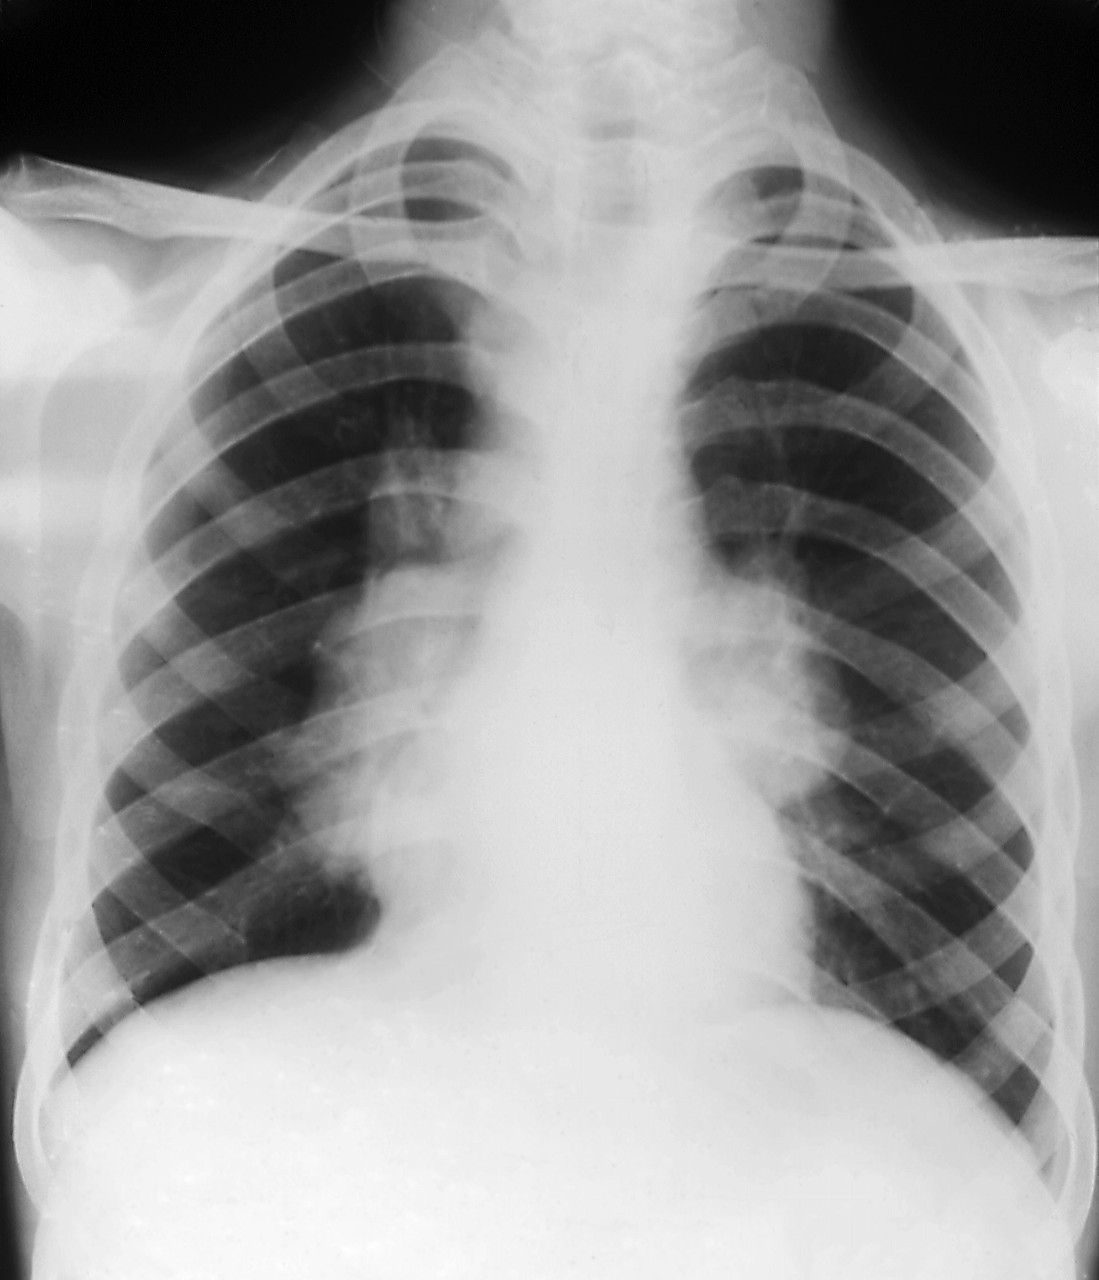

肺结节就是肺部CT影像学,对于肺部小病灶的描述性诊断,其中,80-90%以上直径小于2厘米,也就是说,近80 %的肺磨玻璃结节在就诊时,病灶都不到一个鹌鹑蛋的大小,是一种非常“迷你”的病变。